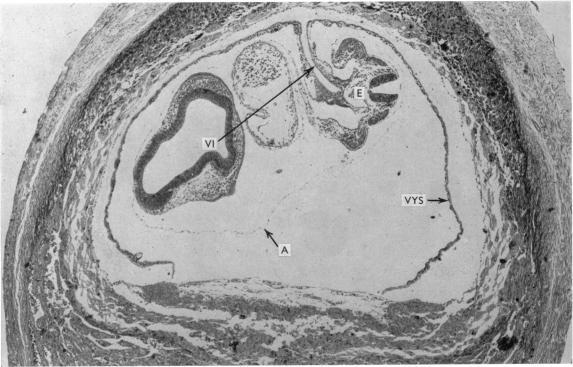

As a contribution to the problem of the immunological privilege of the fetus it was decided to investigate the fate of yolk sac grafts in mice. Ten-day post-coitum mouse visceral yolk sac was transplanted to a dermal tunnel in the flank of isogeneic animals. In this site the yolk sac was capable of surviving for at least 15 days past the normal duration of pregnancy. Yolk sac was transplanted to a similar site in allogeneic animals and was found to be destroyed by an immunological reaction within 13 days. Orthotopic skin grafts between the same strains of mice used in the yolk sac transplantation were rejected in first-set fashion within 13 days. A limited series of host animals, previously sensitized by visceral yolk sac, rejected orthotopic skin grafts in second-set fashion. These findings indicate that the cells of the visceral yolk sac in the mouse contain transplantation antigens. Possible reasons why such antigens do not lead to fetal rejection during pregnancy are considered.

为了研究胎儿免疫特权问题,决定对小鼠卵黄囊移植的命运进行研究。将受孕10天的小鼠内脏卵黄囊移植到同基因动物胁腹的皮肤隧道中。在此部位,卵黄囊能够在超过正常孕期的时间内存活至少15天。将卵黄囊移植到异基因动物的类似部位,发现其在13天内被免疫反应破坏。在卵黄囊移植中使用的相同品系小鼠之间的原位皮肤移植在13天内以初次排斥的方式被排斥。一系列有限的先前经内脏卵黄囊致敏的宿主动物以二次排斥的方式排斥原位皮肤移植。这些发现表明,小鼠内脏卵黄囊的细胞含有移植抗原。文中还考虑了此类抗原在孕期为何不会导致胎儿被排斥的可能原因。